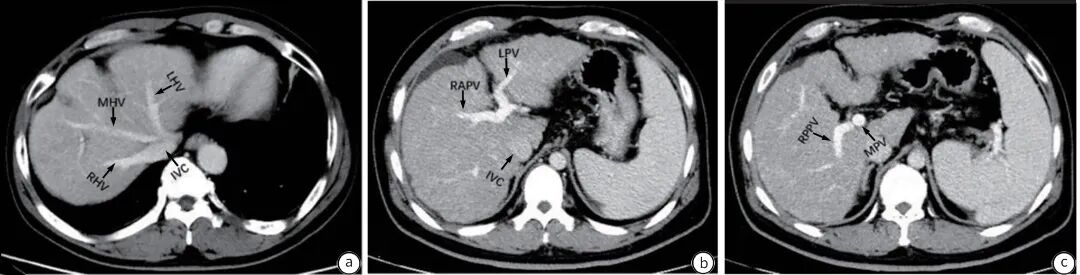

CT检查具有较高分辨率、扫描速度快的特点。平扫能够呈现出不同灰阶影像,增强CT扫描图像更有利于发现周围组织及血管之间的关系。CT常规增强扫描肝脏时通常采用动脉期、门静脉期、实质期三期扫描,观察肝动脉、肝静脉、门静脉和下腔静脉走行、狭窄、血栓或癌栓形成等(图1)。针对部分肝静脉阻塞性疾病,常规三期扫描肝静脉常不能显示,适度延长静脉期扫描时间(>180 s),可增加肝静脉显示,对肝静脉型BCS的诊疗有较高价值。

注: a,增强CT横轴位显示肝静脉层面图;b、c,门静脉及左、右分支层面图。CT,计算机体层成像;IVC,下腔静脉;LHV,肝左静脉;MHV,肝中静脉;RHV,肝右静脉;MPV,门静脉主干;LPV,门静脉左支;RAPV,门静脉右前支;RPPV,门静脉右后支。

图1 肝静脉与门静脉增强CT示意图